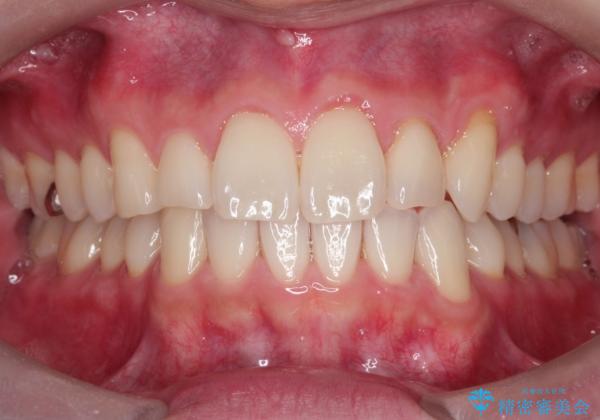

- 前歯の凸凹と顎の偏位を主訴に来院されました。

下顎の偏位を認めましたが、外科矯正を希望されなかったためできる範囲で顎の偏位を治すことができるよう治療を行なっております。

治療開始前に、下顎位の評価をおこなうことで、完成度の高い治療を行うことができました。